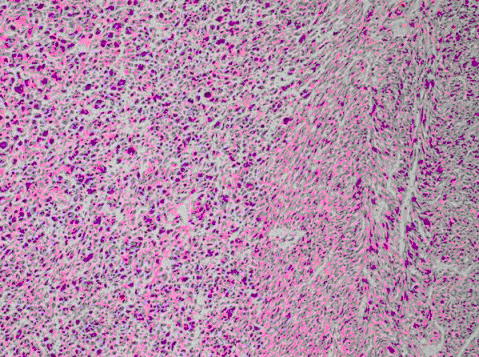

患者,男,67岁。腮腺无痛性肿块。界清、活动,肿瘤切面实性。镜下见肿瘤细胞形态一致,细胞体积较小。呈片状或条索状、核深染。团片周边部细胞呈单层柱状排列,基底膜增厚,PAS阳性。最可能的诊断是

B、基底细胞腺瘤